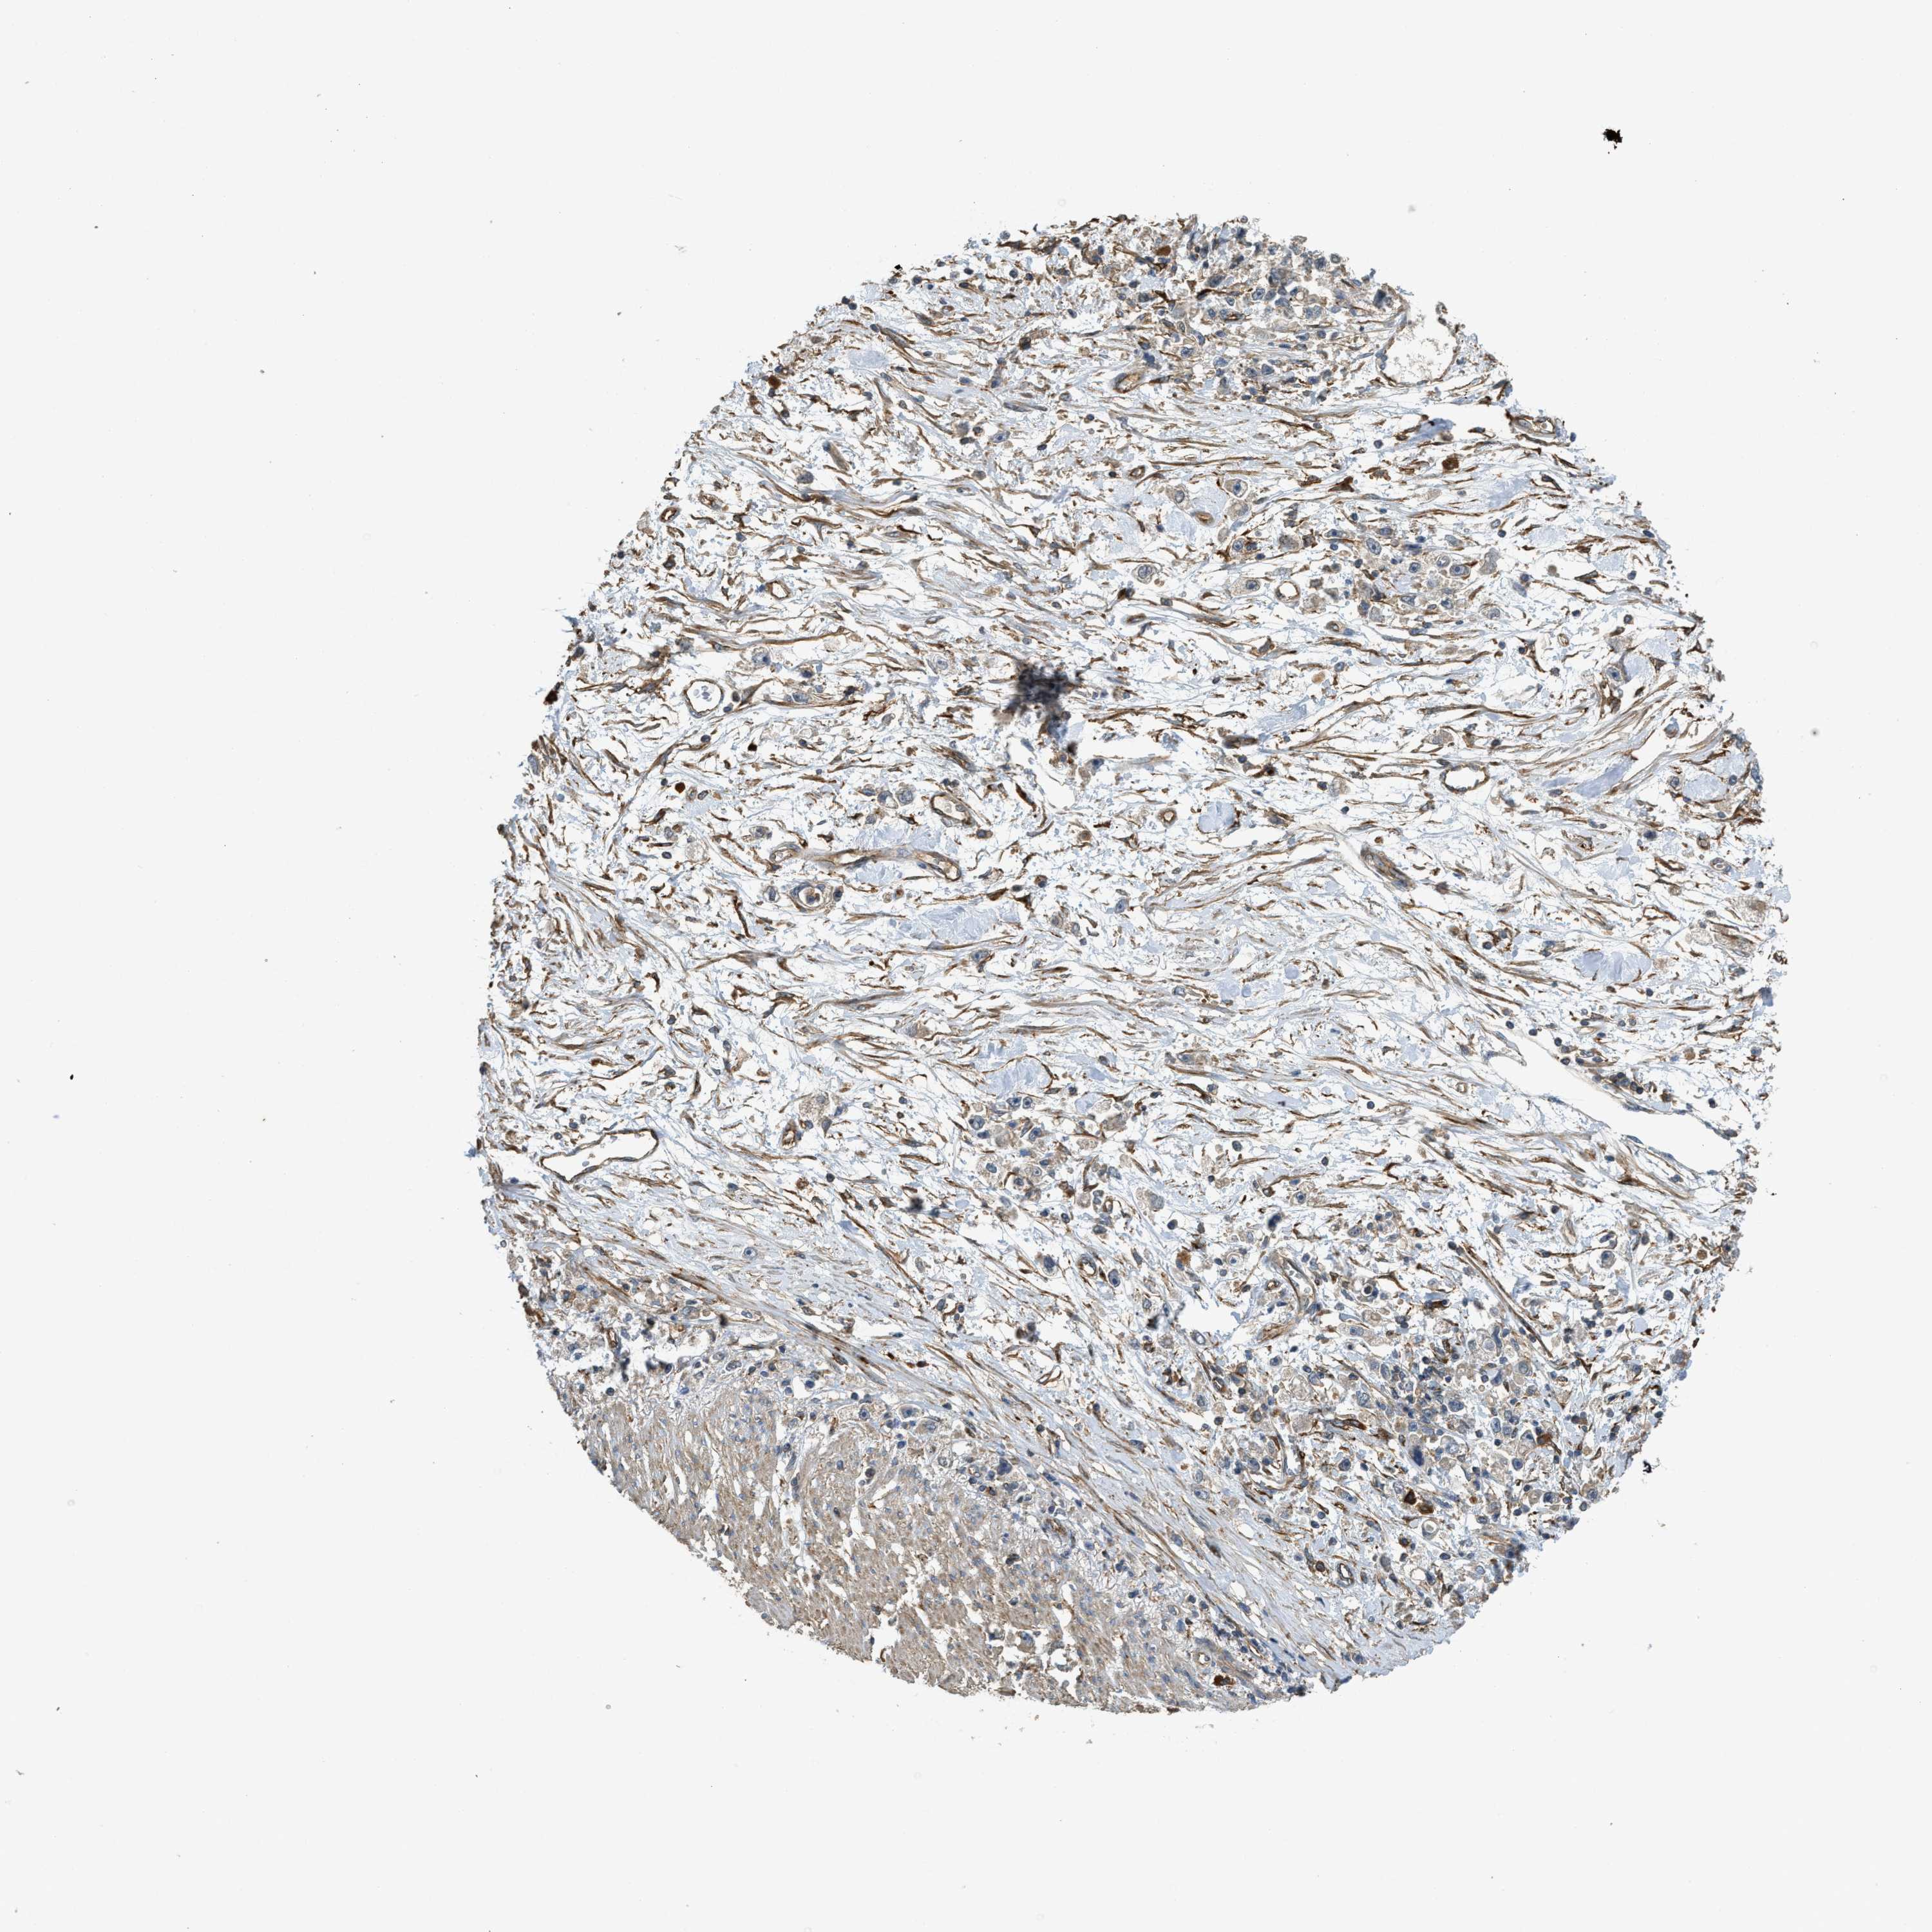

STOMACH CANCER - Protein expressioni

A mouse-over function shows sample information and annotation data. Click on an image to view it in a full screen mode. Samples can be filtered based on level of antibody staining by selecting one or several of the following categories: high, medium, low and not detected. The assay and annotation is described here.

Antibody stainingi

Antibody staining in the annotated cell types in the current human tissue is reported as not detected, low, medium, or high, based on conventional immunohistochemistry profiling in selected tissues. This score is based on the combination of the staining intensity and fraction of stained cells.

Each image is clickable and will lead to virtual microscopy that enables deeper exploration of all samples and also displays staining intensity scores, fraction scores and subcellular localization as well as patient and tissue information for each sample.

Antibody HPA018951

Antibody CAB013716

Adenocarcinoma, NOS

Adenocarcinoma, High grade